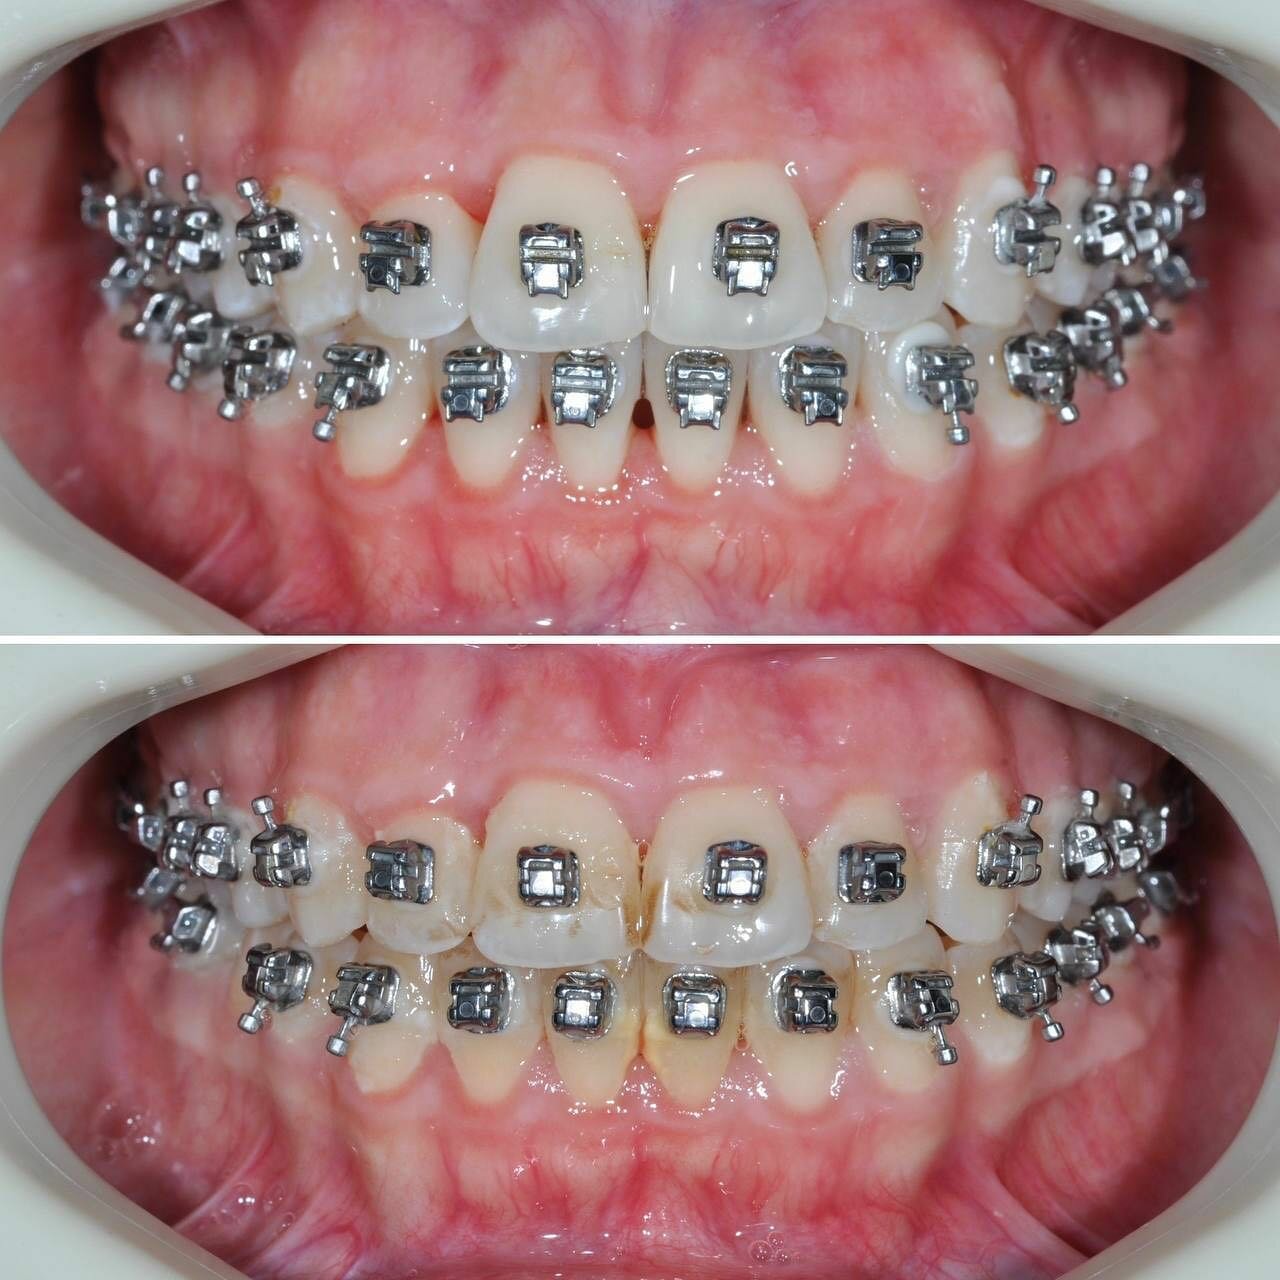

- брекеты

- Положительные впечатления от консультации и установки брекетов.

- Халатность ортодонта (непунктуальность, некачественное лечение).

- Недовольство качеством ортодонтического лечения (потраченные время и деньги без результата)

Ортодонт Эльдар халтурщик не пунктуальный 6 лет и 75 тр на воздух. Не отдавайте всю сумму на перёд а к нему вообще не ходите. Что по мне в шею его гнать надо. И таких как он.

Эльдар безответственно ведет запись.Каждый раз придя в свое время готовьтесь ждать еще пол часа-час!

Записывался на консультацию и дальнейшую установку брекетов для исправления прикуса. Впечатления на данный момент только положительные. Работа аккуратная, отношение вежливое, дополнительных услуг не навязывали.